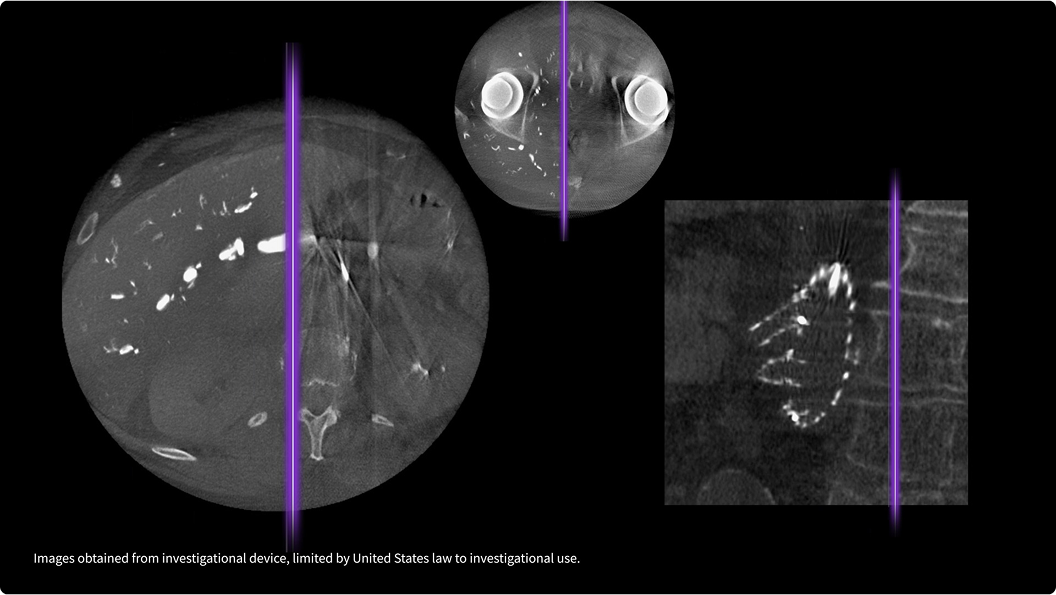

Experience clear images on a range of patients from adult to pediatric with the latest probes for the Venue family.